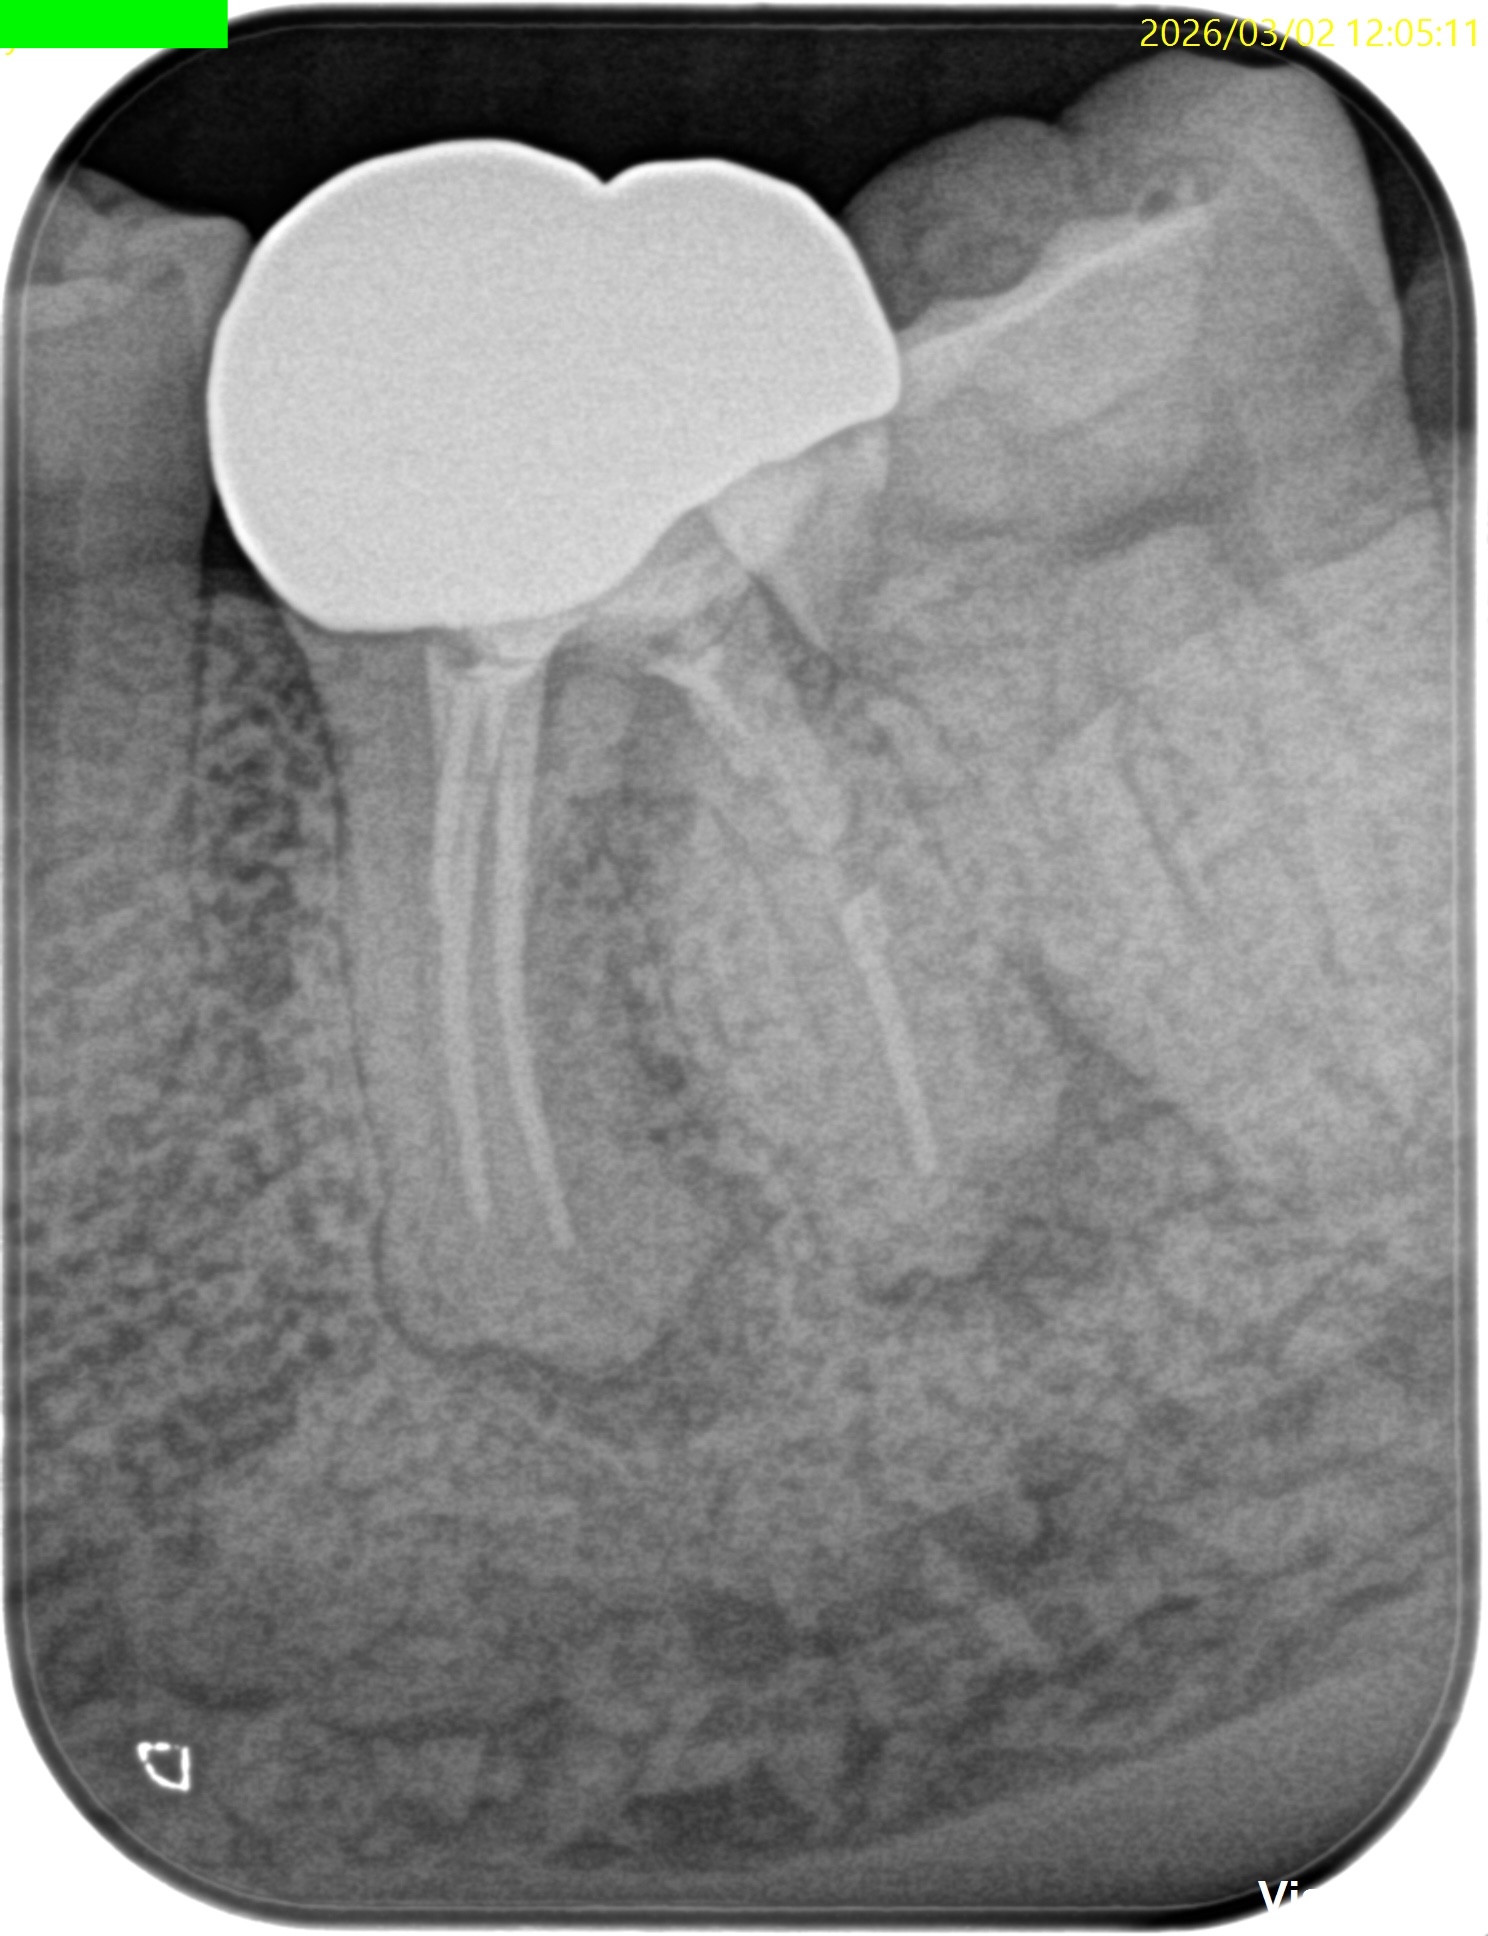

2枚のPAでは何もわからない。

あなたはこの一連の“絵”に気づいただろうか?

この2枚のPAでそれがわかるだろうか?

私にはわからない。

私が気づいたのは、

この絵をみて

違和感

を感じたからである。

穿孔しているのだろうか?とまず思ったが、CBCTをみてそれは穿孔でなく外部吸収の可能性が高いと判断できた。